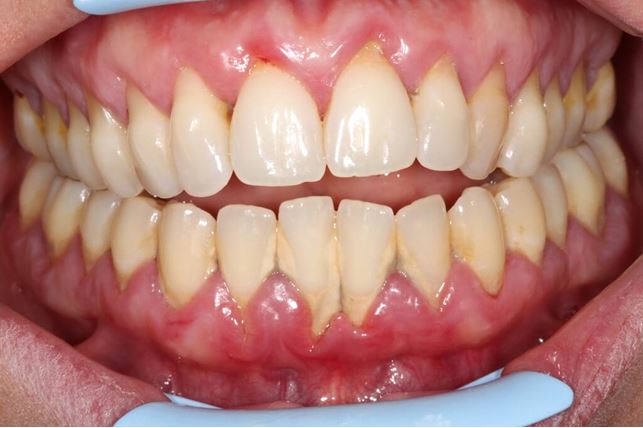

Dziąsła i przyzębie w stanie zapalnym.

Zapalnie zmienione dziąsło jest zaczerwienione i obrzęknięte, niekiedy sine. W początkowych stadiach choroby nie ma bólu. Pacjenci często mówią: nic mnie nie boli, więc chyba jest w porządku. Otóż nie, ból pojawia się dopiero w zaawansowanych a nawet terminalnych stadiach choroby. Od początku natomiast występuje krwawienie. Pamiętajmy więc, że krwawienie pojawiające się przy szczotkowaniu i nitkowaniu zębów jest ważnym sygnałem alarmowym i nie wolno go zaniedbywać. Nawet przy niewielkim podrażnieniu, np. przy myciu, sondowaniu szczeliny dziąsłowej. Powoli stan zapalny nasila się, powstają drobne mikroowrzodzenia nabłonka szczeliny dziąsłowej. Przy dalszym nasileniu choroby zaczynają się formować ropnie przyzębia – definicja: zlokalizowany ropny stan zapalny tkanek przyzębia. Ropnie mogą być pojedyncze i mnogie, ostre, lub przewlekłe, ze względu na lokalizację: dziąsłowe, przyzębne, okołokoronowe i okołowierzchołkowe. Ropnie formują się zwłaszcza tam, gdzie są pionowe ubytki tkanki kostnej, otwarte rozwidlenia korzeni (rozwidlenia korzeni występują u zębów wielokorzeniowych). Znaczącą rolę odgrywają pogorszenie higieny jamy ustnej, współistniejące choroby. Rozległe ropnie powoduje szybką i rozległą destrukcję tkanek przyzębia, w tym kości, co często skutkuje utratą zęba, zwłaszcza u osób z zaawansowaną chorobą i ubytkiem kostnej otaczającej zęby. Ważna uwaga! Rozważmy sytuację: pacjent zauważa krwawienie z dziąseł przy zabiegach higienicznych, przy posiłkach. Gdzie kierujemy pierwsze kroki? … Do Internetu. Korzystanie z porady dr Google może / musi nas jednak ukierunkować na zakup pasty do zębów, prawdopodobnie tej, która jest aktualnie najlepiej pozycjonowana w wynikach wyszukiwania. Jeżeli składniki farmakologiczne zawarte w paście stłumią krwawienie, może to uśpić nasza czujność i odwlec w czasie wizytę u lekarza stomatologa. W tym czasie choroba, pomimo braku objawów uchwytnych przez pacjenta, przy zmniejszonym krwawieniu, rozwija się w ukryciu. Zmniejsza to nasze szanse na szybkie podjęcie skutecznej terapii.

Zapalenie dziąsła jest uleczalne, to znaczy można go wyleczyć, bez trwałych następstw anatomicznych. W początkowym okresie dochodzi do przekrwienia i obrzęku brodawek dziąsłowych, dziąsła brzeżnego, Tkanki dziąsła stają się bolesne, łatwo krwawią przy szczotkowaniu, przy drobnych urazach mechanicznych podczas przyjmowania posiłków, itp.